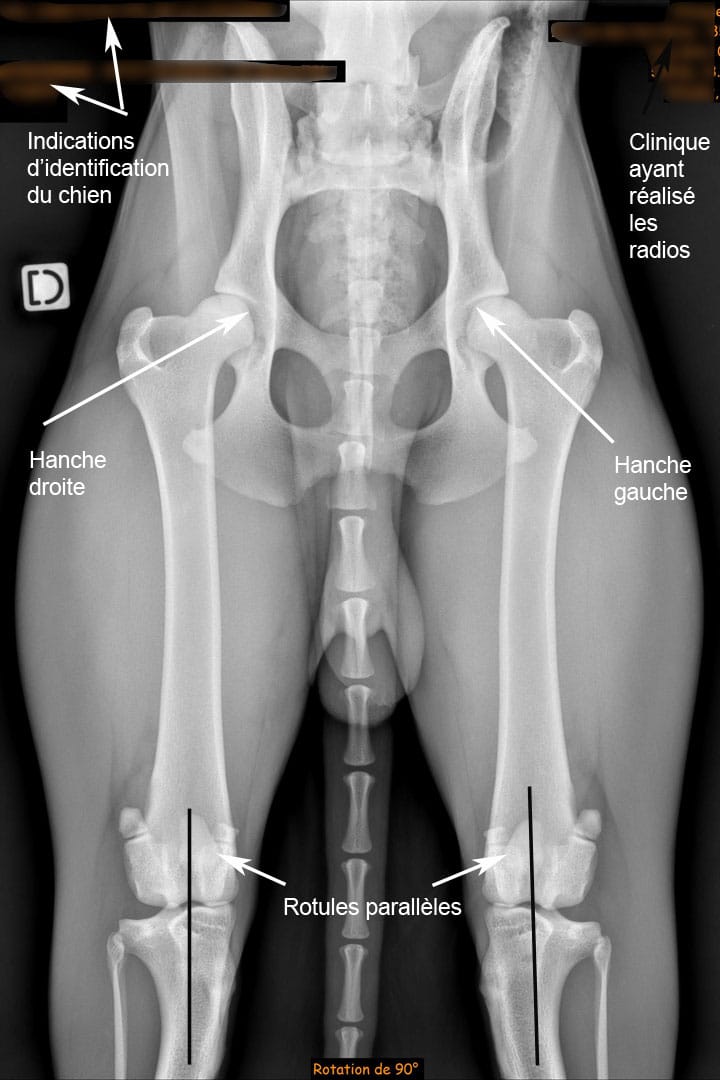

Le positionnement précis du chien

La position standardisée est cruciale pour une interprétation correcte :

• Le chien est allongé sur le dos, dans une gouttière adaptée.

• Les fémurs doivent être parallèles.

• Les rotules sont centrées, et le bassin parfaitement symétrique.

Seul un positionnement rigoureux permet d’évaluer la congruence articulaire et la présence éventuelle de lésions.

Pour qu’un cliché radiographique soit validé dans le dépistage de la dysplasie de la hanche chez le chien, deux exigences majeures doivent être respectées : l’identification du chien et la qualité technique de l’image.

La précision du diagnostic dépend d’une image parfaitement réalisée. Une anesthésie générale est quasi-systématique pour garantir un positionnement rigoureux du chien. Les critères techniques à respecter sont :

• Un bassin parfaitement symétrique, vérifié par l’égalité de largeur des ailes de l’ilium

• Des fémurs droits et parallèles

• Des rotules visibles et centrées entre les condyles fémoraux

• Une image nette, avec des contours osseux bien définis

• Une visibilité complète des articulations coxo-fémorales et des grassets (genoux)